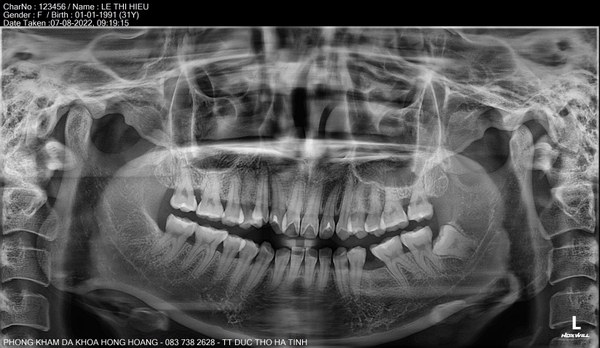

𝐇𝐈̀𝐍𝐇 𝐀̉𝐍𝐇 𝐂𝐇𝐔̣𝐏 𝐏𝐀𝐍𝐎𝐑𝐀𝐌𝐀 (𝐑𝐀̆𝐍𝐆 𝐓𝐎𝐀̀𝐍 𝐂𝐀̉𝐍𝐇) 𝐕𝐀̀ 𝐂𝐄𝐏𝐇𝐀𝐋𝐎 𝐁𝐀̆̀𝐍𝐆 𝐌𝐀́𝐘 𝐂𝐇𝐔̣𝐏 𝐂𝐀̆́𝐓 𝐋𝐎̛́𝐏 𝐕𝐈 𝐓𝐈́𝐍𝐇 𝐑𝐀̆𝐍𝐆 𝐇𝐀̀𝐌 𝐌𝐀̣̆𝐓.

🍀Hình ảnh chụp phim panorama và cephalo (mặt thẳng, mặt nghiêng) giúp bác sỹ răng hàm mặt đánh giá phân tích được khung hàm trên của bệnh nhân và lập kế hoạch điều trị chuẩn xác.

- Toàn cảnh ( panorama) : giúp nhìn thấy các trục chân răng, răng ngầm, các bệnh lý trong xương, tương quan lồi cầu 2 bên, hình dạng lồi cầu, các răng bệnh lý.